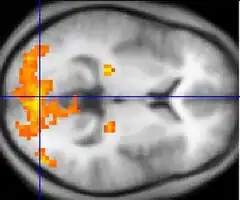

Asperger syndrome appears to result from developmental factors that affect many or all functional brain systems, as opposed to localized effects.[72] Although the specific underpinnings of AS or factors that distinguish it from other ASDs are unknown, and no clear pathology common to individuals with AS has emerged,[12] it is still possible that AS's mechanism is separate from other ASDs.[73] Neuroanatomical studies and the associations with teratogens strongly suggest that the mechanism includes alteration of brain development soon after conception.[68] Abnormal fetal development may affect the final structure and connectivity of the brain, resulting in altered neural circuits controlling thought and behavior.[74] Several theories of mechanism are available; none are likely to provide a complete explanation.[75]

The underconnectivity theory hypothesizes underfunctioning high-level neural connections and synchronization, along with an excess of low-level processes.[70] It maps well to general-processing theories such as weak central coherence theory, which hypothesizes that a limited ability to see the big picture underlies the central disturbance in ASD.[76] A related theory—enhanced perceptual functioning—focuses more on the superiority of locally oriented and perceptual operations in autistic individuals.[77]

The mirror neuron system (MNS) theory hypothesizes that alterations to the development of the MNS interfere with imitation and lead to Asperger's core feature of social impairment.[71][78] One study found that activation is delayed in the core circuit for imitation in individuals with AS.[79] This theory maps well to social cognition theories like the theory of mind, which hypothesizes that autistic behavior arises from impairments in ascribing mental states to oneself and others;[80] or hyper-systemizing, which hypothesizes that autistic individuals can systematize internal operation to handle internal events but are less effective at empathizing when handling events generated by other agents.[81]